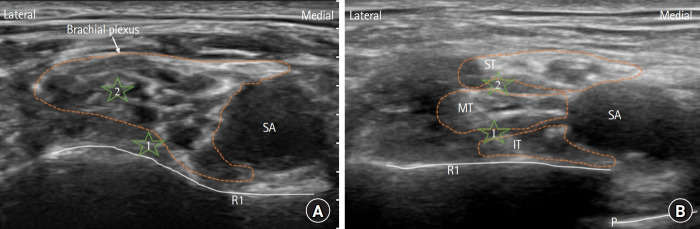

背景:由于锁骨上阻滞的截间入路(IA-SCB)的特征不确定,我们旨在比较其在阻滞后30分钟内与经典入路(CA)对感觉-运动阻滞的影响。方法:总共122例接受肘部、前臂、手腕或手部手术的患者被随机分配接受CA-SCB或IA-SCB。两组均给予相同的局麻药(1%利多卡因和0.5%罗哌卡因),共25 ml。IA-SCB组在中下干间注射15 ml,在上中干间注射10 ml, CA-SCB组在角袋注射15 ml,在神经簇中央注射10 ml。所有四个末梢神经的感觉-运动阻滞每5分钟评估一次,持续30分钟。非劣效阈值旨在排除IA-SCB在阻滞后20分钟完全感觉阻滞的患者比例比CA-SCB低约5%的可能性。结果:CA-SCB和IA-SCB在阻滞后20分钟完全感觉阻滞分别为79.3%和72.7%,超过了-5%的非劣效边际(-6.6%,95% CI[-22.3%至9.1%];非劣效性P值= 0.206)。此外,IA-SCB表现为下肌皮神经阻滞,表现时间较长,半膈肌轻瘫发生率较高。结论:我们的研究结果并不能证实IA-SCB在阻滞后20分钟实现完全感觉阻滞方面对CA-SCB的非劣效性。可能需要进一步的研究来确定其在区域麻醉中的作用。

Methods: In total, 122 patients undergoing elbow, forearm, wrist, or hand surgery were randomly assigned to receive CA-SCB or IA-SCB. Both groups received identical local anesthetic agents (1% lidocaine and 0.5% ropivacaine) in 25 ml total. The IA-SCB group received 15 ml between the middle and inferior trunks and 10 ml between the superior and middle trunks, while the CA-SCB group received 15 ml in the corner pocket and 10 ml in the center of the neural clusters. Sensory-motor blockade of all four terminal nerves was assessed every 5 min for 30 min. The non-inferiority threshold aimed to exclude the possibility that the IA-SCB was > 5% inferior to the CA-SCB in terms of the proportion of patients with complete sensory blockade at 20 min post-block.